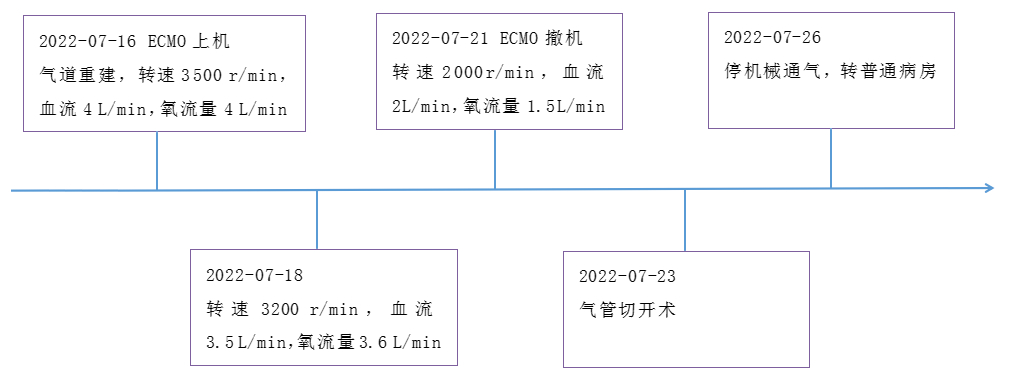

入院查体:患者意识清,烦躁不安,体温36.2℃,心率112次/min,呼吸38次/min,血压107/72 mmHg(1 mmHg=0.133 kPa),SPO2 92%,颈部肿胀淤血;颈部、胸部、腹壁下多发捻发感;双肺叩诊呈鼓音;听诊双肺呼吸音消失。辅助检查:血气分析:氧分压(PO2)51.3 mmHg,二氧化碳分压(PCO2)67.2 mmHg,碱剩余(BE)-8.4 mmol/L,pH 7.15,乳酸4.5。血常规:HGB 104 g/L。头颅+胸部CT:脑沟、脑裂及脑室多发积气,主支气管塌陷,两侧支气管闭塞,两侧气胸伴部分肺组织膨胀不全,肺压缩70%,两侧多发肋骨骨折,两侧胸壁大量皮下气肿,右侧肩胛骨骨折,右侧锁骨骨折。床旁超声检查未见心肌收缩减弱,心包、胸腹腔未见明显积液(图 1)。初步诊断:主支气管断裂、双侧血气胸、肺挫伤,多发肋骨骨折,呼吸衰竭。就诊过程中患者出现意识不清,呼之不应,氧饱和进行性下降至65%,心率减慢至23次/min,监护仪提示室性逸搏心律,立即行心肺复苏、气管插管、双侧胸腔闭式引流、止血、补液等抢救,复苏10 min后患者恢复R0SC,结合检验检查考虑考虑主气管塌陷致急性呼吸衰竭而引起呼吸心搏骤停,急邀区域创伤中心多学科团队(multiple disciplinary team,MDT)远程会诊后建议行主气道修补术以改善患者通气维持机体氧供,但该院无手术条件需转上级医院,而经过积极对症治疗后患者病情无好转,呼吸机控制呼吸下(容量控制模式,潮气量8 mL/kg,呼吸频率42次/min,呼气末正压10 mmHg,氧浓度100%),氧合指数(PaO2/FiO2)持续下降至50 mmHg以下,血乳酸上升至8.2 mmol/L,达到(extracorporeal membrane oxygenation,ECMO)支持指征[1],急诊行体外膜肺氧合治疗,采用V-V ECMO(veno-venous ECMO)模式,选择右侧股静脉及右侧颈内静脉,右侧股静脉置入20Fr引血导管,右侧颈内静脉置入19Fr回血导管,使用迈柯唯公司ROTAFLOW离心泵及QUADROX PLS氧合器,设置参数:转速3500 r/min,血流量4 L/min,氧流量4 L/min,患者氧饱和度维持于90%左右。遂在呼吸机及ECMO支持下由救护车护送至本院EICU。

到达我院后由绿色通道急送手术室,心胸外科急行气管修补术,ECMO维持下氧饱和度约93%,经颈部正中切口,术中见主气管上第一、二气管软骨间的气管膜部完全性离断,术中停止呼吸机支持,终止肺通气,完全由ECMO替代,探查上下断端,将断裂膜部与前方气管软骨缝合以完成气管重建。术后转入EICU。ECMO运行中使用肝素抗凝,抗凝策略:肝素125~375 U/h,激活全血凝固时间(activated clotting time of hole blood,ACT)维持在100~140 s,监测HGB稳定于85~101 g/L,5 d后患者病情好转,循环稳定,遂予停用ECMO。7 d后患者意识状态无好转,咳痰能力欠佳,经气管导管吸痰时吸痰导管仅能置入约20 cm,遂予气管镜检查,纤维气管镜探至气管修补处时发现气管软骨下陷导致气道狭窄(图 2),联系耳鼻咽喉科行气管切开术,经颈部正中切口,在下陷气管软骨下置入气管套管,术后予以呼吸机脱机锻炼。10 d后复查胸部CT与入院时相比较,双肺渗出、肺不张、胸腔积液支气管塌陷及胸壁皮下气肿情况均好转(图 3),停机械通气转普通病房康复治疗。

| 图 4 ECMO辅助时间节点 |